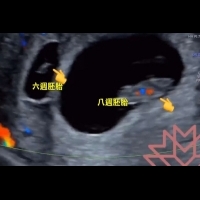

婦產科醫師蘇怡寧在臉書上Po出超音波影片,這名30多歲的孕婦子宮內,有一大一小胚胎,大的8週,小的6週,神奇的是,這位媽咪是第八週產檢的時候,才意外發現另一個六週的胚胎,醫師還寫下兩週前確定只有看到一個,研判這是分別在兩週先後著床的雙胞胎,還說在生理期荷爾蒙調控的機轉上這很難發生,相當罕見!

女性懷孕後竟然還能排卵受孕,歷史上幾乎沒有案例可循,不過光是從影片上來看,有其他醫師認為也有可能是營養不均的異卵雙胞胎。

醫師有不同見解,到底真相為何,恐怕得等小孩出生往上追蹤才有解答,畢竟兩週的時間,都還在偏差範圍內,不過對父母來說,家裡意外多了一名新成員,肯定是又驚又喜。